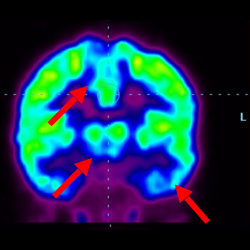

細胞治療后,藍色和黑色區域減少,并且看到更活躍的區域。這表明損傷減少并改善了大腦功能。

細胞治療前 PET CT 掃描顯示神經組織中的藍/黑色區域,表明腦癱引起的大腦損傷。

這證明細胞療法是治療腦癱兒童安全有效的方法。細胞療法可以更新大腦損傷的核心,并且可以通過 PET CT 掃描來監測大腦的改善情況。這些細胞療法與標準治療一起促進腦癱兒童的生長和改善。